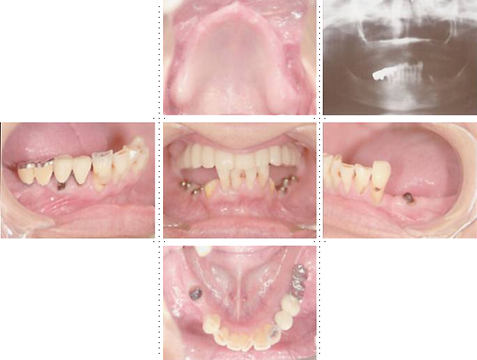

症例3

73才 男性

上顎2本、下顎1本だけ歯が残り、入れ歯を使っておりますが、痛みがありよく噛めない状態。

上顎1本の歯だけを残し、インプラント8本埋入。下顎は歯を抜き、インプラント7本埋入。上下顎とも、セラミック(MB)クラウンをセット。仕事・生活ともに活力が出て、新しい人生が始まったようであると喜んでいただきました。